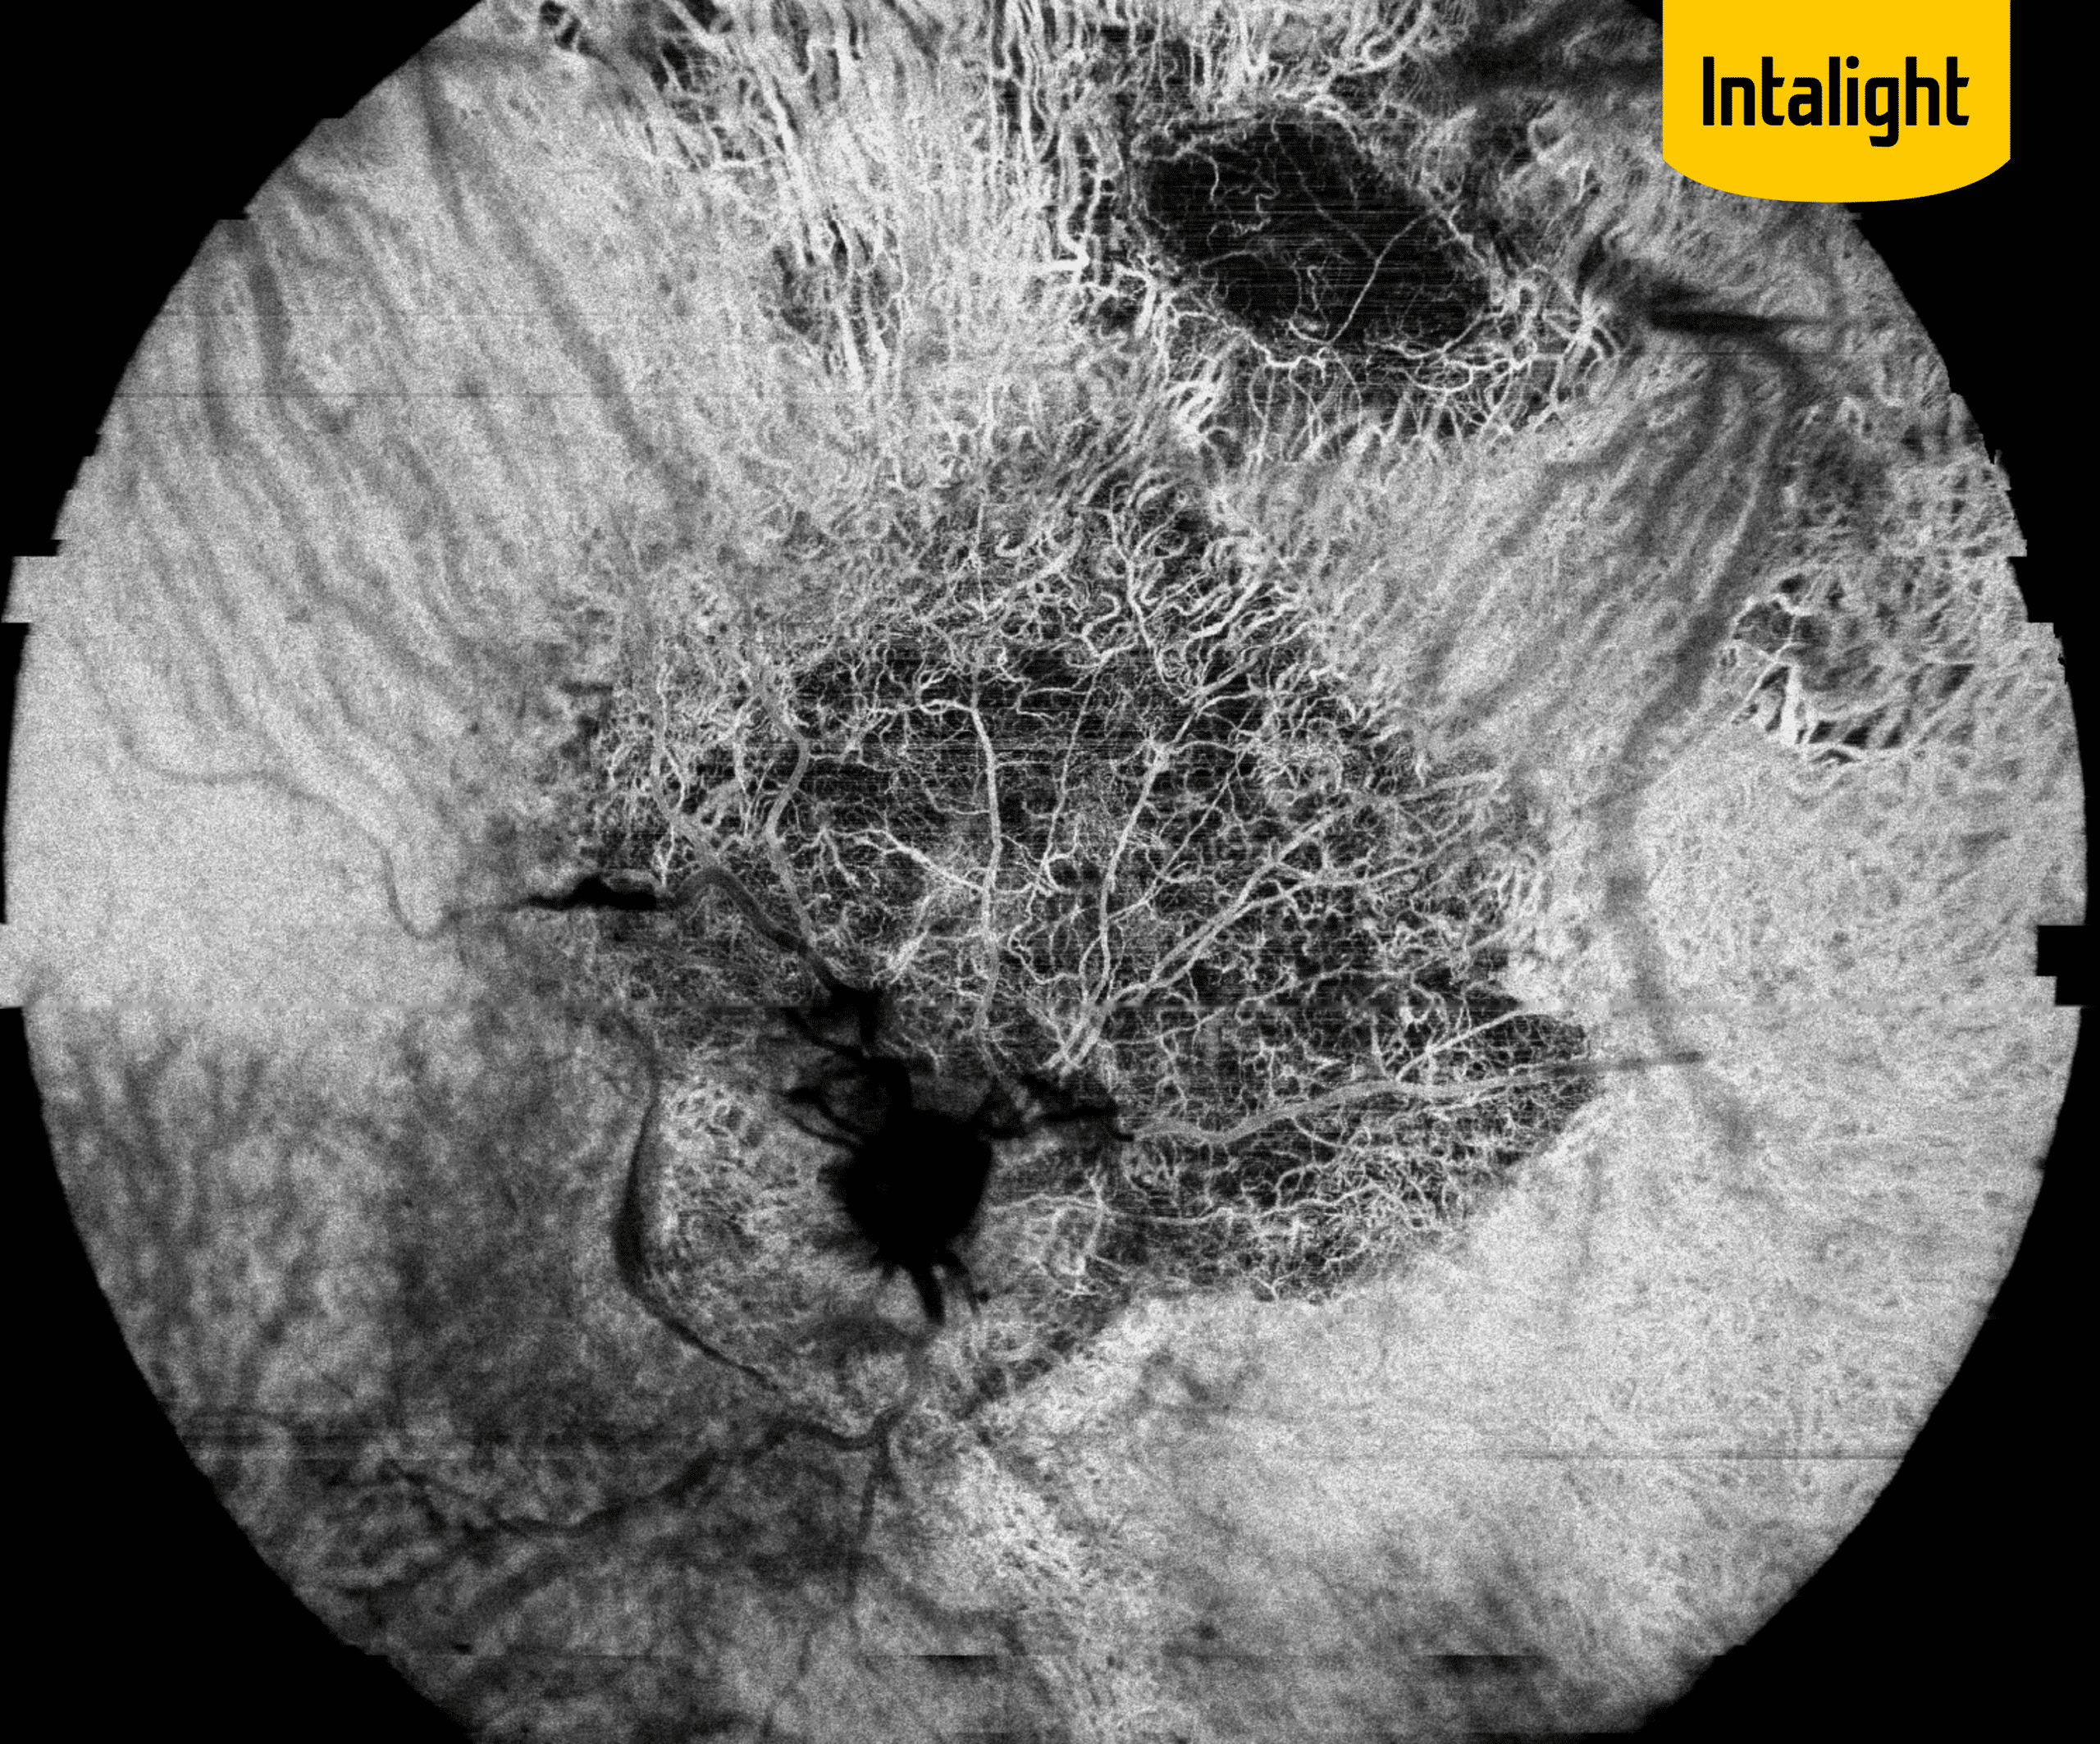

DMLA et vasculopathies : nouveaux regards sur le pôle postérieur grâce au DREAM OCT